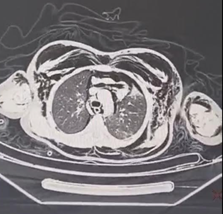

CT scanner revealed a tracheal rupture of the posterior edge of the cervicothoracic trachea at the level of C7-T1, approximately 4 mm in length, complicated by a pneumomediastinum without involvement of the mediastinal organs, as well as significant subcutaneous emphysema. low-volume both sides pneumothorax (Figure 3). There was no pulmonary parenchymal abnormality, nor at the level of the cervical spine or rib cage.

Figure 3: CT scanner shows a pneumomediastinum without involvement of the mediastinal organs, as well as significant subcutaneous emphysema. Low-volume both sides pneumothorax.